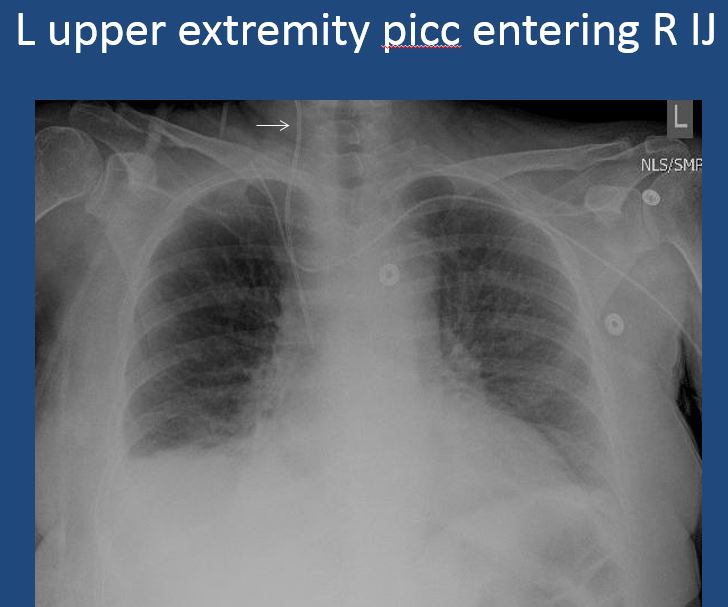

75 year old male with heart disease; PICC placementExam

There is a venous line or lines present and in an improper location or other abnormality. |

no | NA |